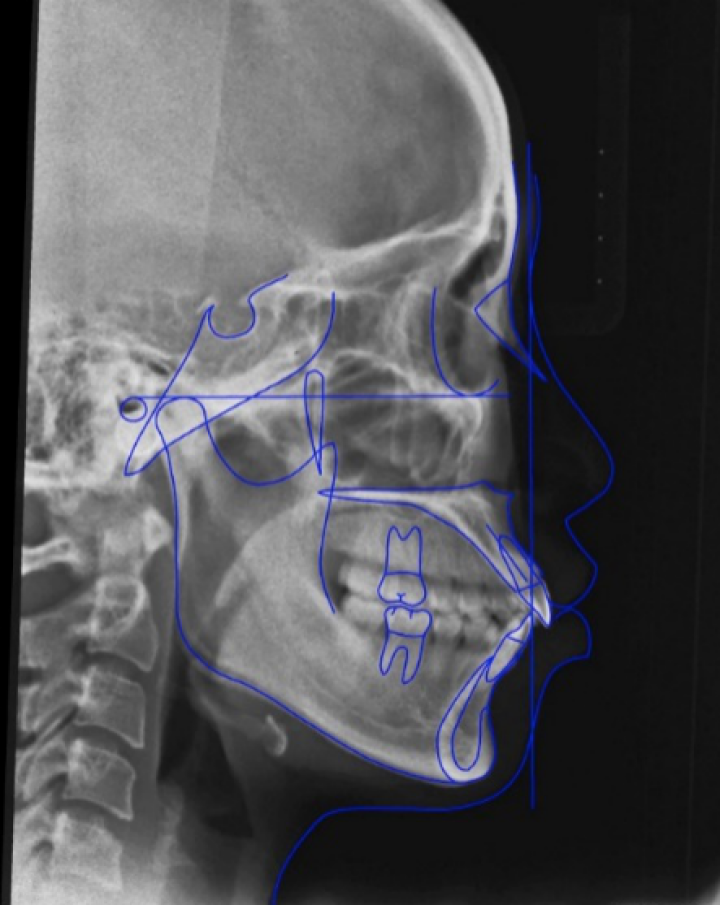

再来从正畸角度说说什么情况下需要拔牙呢?首先并不是所有人都需要拔牙矫正,具体要根据个人的牙齿及颌骨情况来决定。常见拔牙的两种情况:1.牙齿拥挤,需要通过拔牙提供间隙用于排齐;2.牙齿前突,需要拔牙提供间隙内收前牙。最常见的拔牙位置是第一或二前磨牙,某些特殊情况下(如残冠残根无法保留)也会选择拔除其他位置的牙齿。牙齿拔除后的间隙通过矫正最后得以关闭,对于进食及牙齿健康并无影响。